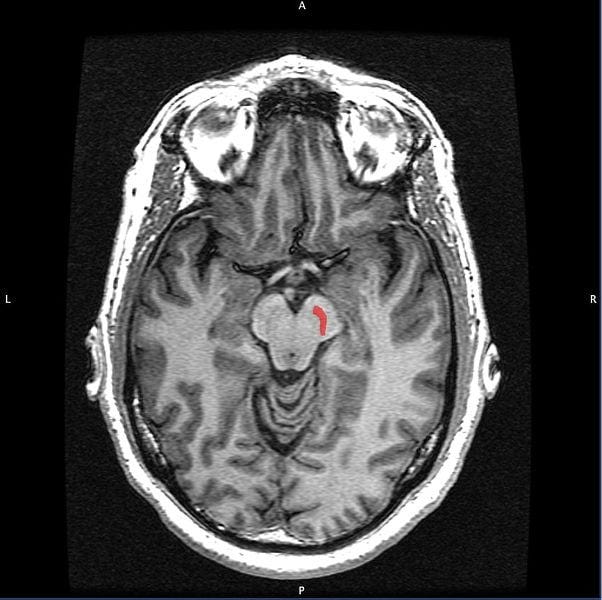

Parkinson’s is caused by the death of dopamine neurons in a small area of the brain called the substantia nigra (shown in red in the MRI below).

This part of the brain is one of the regions responsible for movement amongst other functions. We normally lose 5-10% of the neurons in this brain area per decade of adult life. PD occurs when we hit a threshold of 70% neuron loss in this area, which most people do not surpass in their lifetime. However, losing these neurons is what causes “Parkinsonian signs” and is a major reason why we slow down as we age.